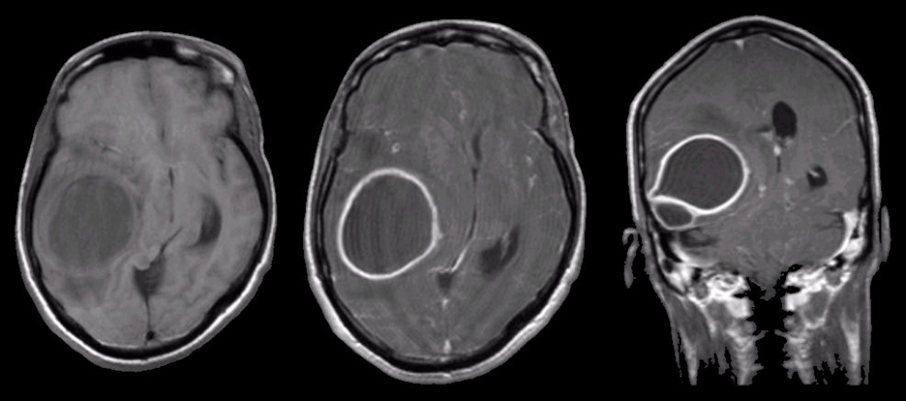

Для подтверждения диагноза внутримозгового кровоизлияния и определения дальнейшей тактики лечения требуется экстренная нейровизуализация. «Золотым стандартом» в первые часы является компьютерная томография (КТ) головного мозга. Этот метод позволяет очень быстро и точно увидеть свежую кровь в ткани мозга, определить объем и расположение гематомы. КТ является первоочередным исследованием, так как позволяет отличить геморрагический инсульт от ишемического, лечение которых кардинально различается.

Магнитно-резонансная томография (МРТ) также используется в диагностике ВМК, но чаще на более поздних этапах. МРТ дает более детальное изображение структур мозга и может помочь в определении причины кровоизлияния, например, выявить опухоль или признаки амилоидной ангиопатии. Для поиска сосудистых аномалий, таких как аневризмы или АВМ, применяется КТ-ангиография или МР-ангиография — исследования сосудов с введением контрастного вещества.